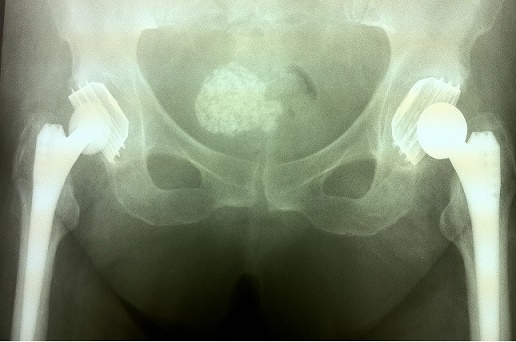

Двухстороннее протезирование тазобедренных суставов. Есть и еще одна патология....